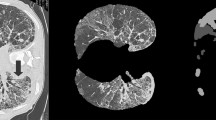

The ongoing COronaVIrus Disease 2019 (COVID-19) pandemic carried by the SARS-CoV-2 virus spread worldwide in early 2019, bringing about an existential health catastrophe. Automatic segmentation of infected lungs from COVID-19 X-ray and computer tomography (CT) images helps to generate a quantitative approach for treatment and diagnosis. The multi-class information about the infected lung is often obtained from the patient’s CT dataset. However, the main challenge is the extensive range of infected features and lack of contrast between infected and normal areas. To resolve these issues, a novel Global Infection Feature Network (GIFNet)-based Unet with ResNet50 model is proposed for segmenting the locations of COVID-19 lung infections. The Unet layers have been used to extract the features from input images and select the region of interest (ROI) by using the ResNet50 technique for training it faster. Moreover, integrating the pooling layer into the atrous spatial pyramid pooling (ASPP) mechanism in the bottleneck helps for better feature selection and handles scale variation during training. Furthermore, the partial differential equation (PDE) approach is used to enhance the image quality and intensity value for particular ROI boundary edges in the COVID-19 images. The proposed scheme has been validated on two datasets, namely the SARS-CoV-2 CT scan and COVIDx-19, for detecting infected lung segmentation (ILS). The experimental findings have been subjected to a comprehensive analysis using various evaluation metrics, including accuracy (ACC), area under curve (AUC), recall (REC), specificity (SPE), dice similarity coefficient (DSC), mean absolute error (MAE), precision (PRE), and mean squared error (MSE) to ensure rigorous validation. The results demonstrate the superior performance of the proposed system compared to the state-of-the-art (SOTA) segmentation models on both X-ray and CT datasets.

Graphical abstract